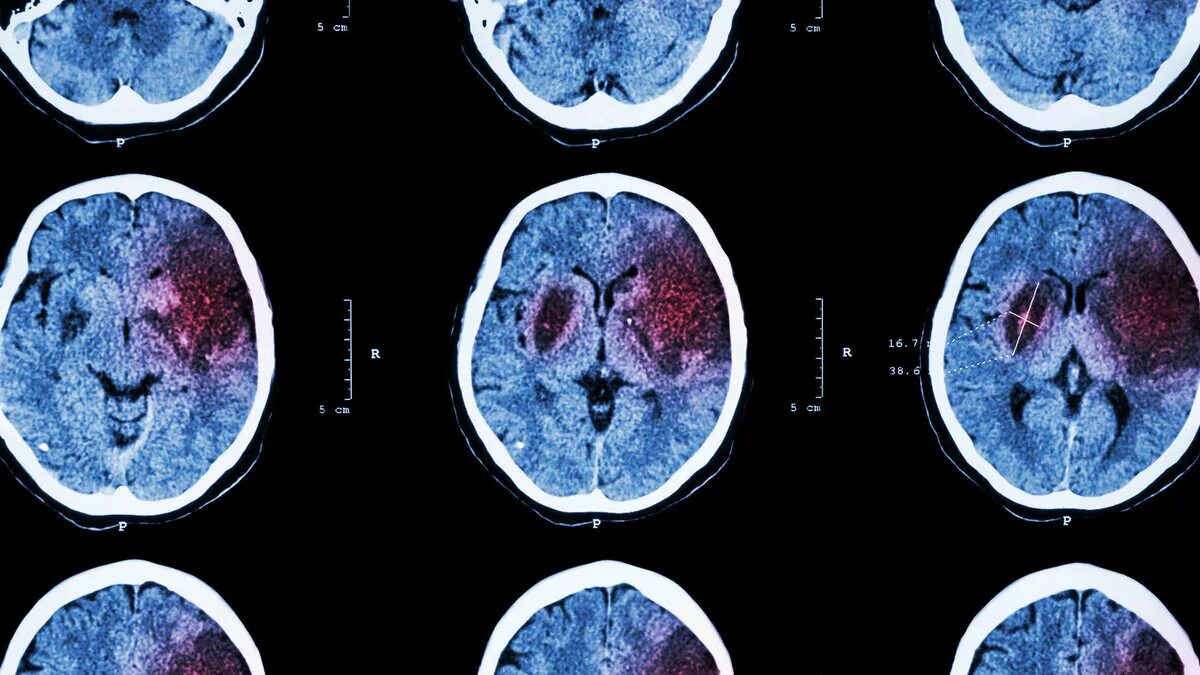

Реабилитация после ишемического инсульта головного мозга